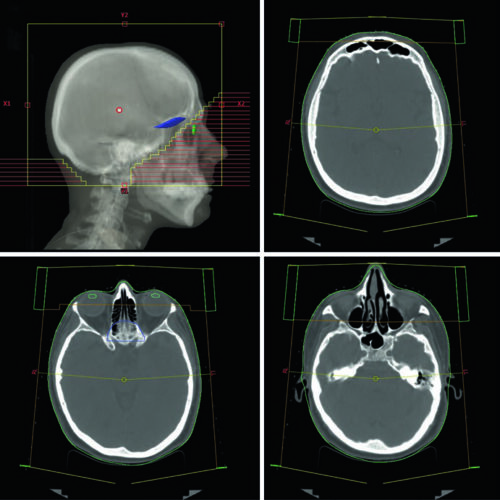

Guias práticos de delineamento de volumes-alvo e órgãos de risco por sítio anatômico na radioterapia.